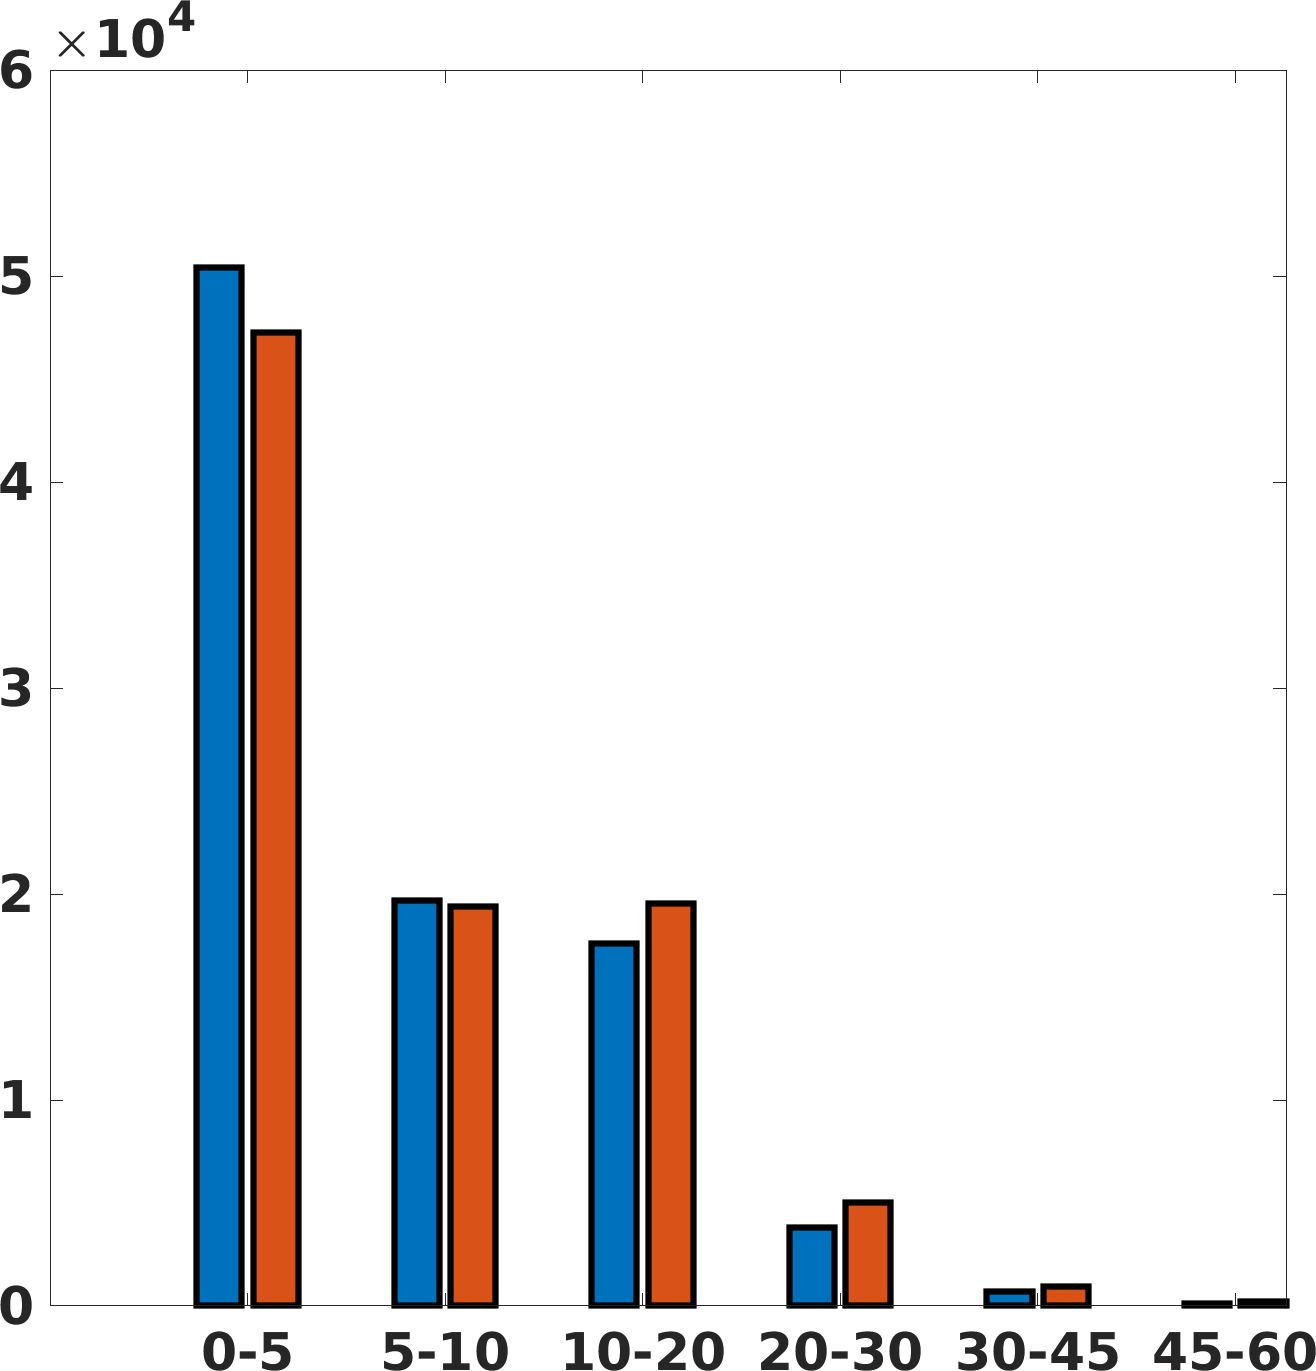

Fig. 17 (left) shows the box plot of the quantitative metrics, comparing the target images with the prediction and the Cubic convolution, respectively. The PSNR metric is computed on a data set of 200 images, belonging to the same district, and with the same up-sampling factor. Analysing the obstetric anatomical district and concerning the corresponding raw images (Fig. 7 (a, left)), the denoising allows the network to significantly improve the results of the up-sampling and the prediction. In particular, comparing the target images with the predicted images, the median PSNR value of obstetric 2X denoised images is 51.8, compared to the median PSNR value of obstetric 2X raw images which is 36.9.

Fig. 17 (right) shows the histogram of the absolute value of the error with respect to the target, of the prediction and Cubic convolution respectively. This result shows that our framework increase of and (2X and 4X, respectively) the number of pixels where the prediction error is lower than 5, which is very similar to the target when visually analysing the images, and improved with respect to the learning framework applied to raw images. According to Fig. 18, our method improves the accuracy of Cubic convolution. For example, the SSIM increases of on cardiac 2X and the MAE increases of on abdominal 4X.